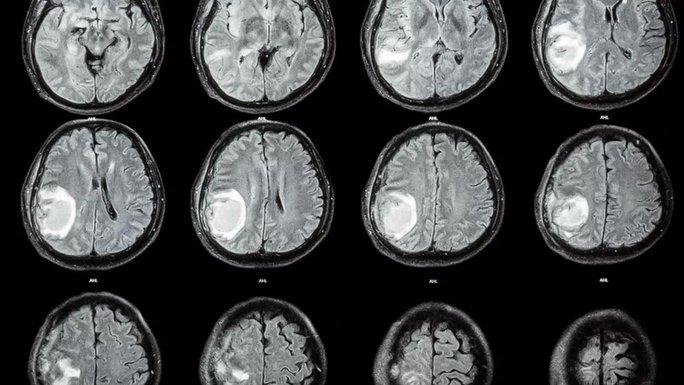

Nghiên cứu dẫn đầu bởi bác sĩ thần kinh học Zongze Li từ Phòng thí nghiệm Peng Cheng (Thâm Quyến - Trung Quốc) cho biết bệnh nhi giấu tên được kiểm tra bằng CT scan khi có những dấu hiệu chậm phát triển thần kinh vận động, đầu to lên bất thường, ứ dịch.

Các hình ảnh cho thấy một khối u lạ xuất hiện trong não đứa trẻ, được xác định là một bào thai vì có cột sống và hai chương chân, cũng như cho thấy thai nhi đó là một thai bị dị tật nứt đốt sống. Thai nhi cũng đã phát triển một chồi chi trên và cấu trúc giống ngón tay.

Hình ảnh CT scan đầu của đứa trẻ 1 tuổi - Ảnh: NEUROLOGY